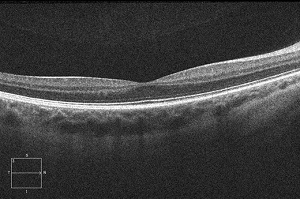

menschlichen Auges (mit freundlicher Genehmigung der Augenklinik des Städtischen Klinikums Karlsruhe) |

Optische Kohärenztomographie (OCT)